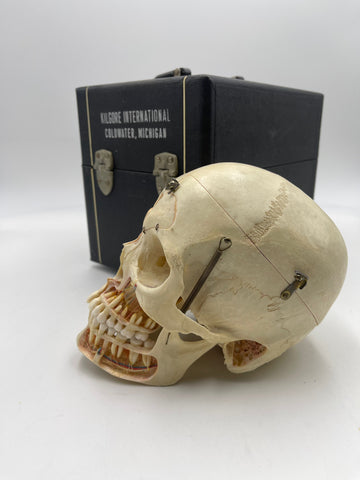

This skull is a stunning representation of the work done by H. Gumpert, a famous skull detailer at the height of medical bone preparations. This skull also presents with a metopic suture: a frontal suture going up the center of the frontal bone, generally complete closure of this happens at 9 months of age, making it a very rare feature.

Very robust, intricately cut and assembled, displaying all dentitions and no missing pieces or breaks. Bone quality is very dense and sturdy, no fragility present.

Large adult male skull likely prepared by the company Clay Adams (stamp on skullcap is too worn to read). Prominent jawline and nasal bridge.

As a Sagittal demonstration skull there are many cutaways and doorways with high quality hardware. Internal orbital cutaways are present and prepared with incredible precision. Nerve pathways of teeth are all present and situated correctly.